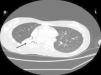

Case reportA female patient with a congenital muscular dystrophy had been treated with nocturnal nasal noninvasive positive pressure ventilation (NIV) since she was 20. At the age of 26 she was hospitalised for a complete atelectasis of the right lower lobe, and had recovered after more than a month with the application of an intensive combined protocol of HFCWO (The Vest Airway Clearance System, Hill-Rom St. Paul, MN, USA) plus manual and mechanical assist cough (In-Exsufflator, Cough-Assist®, Philips Respironics, Murrysville, PA, USA). Her clinical condition remained good until the age of 28, when her lung function tests showed the following values: vital capacity 0.55 L (16% of the predicted value), maximal inspiratory pressure 10cmH2O (11% of predicted), maximal expiratory pressure 14cmH2O (13% of predicted), and peak cough expiratory flow 80L/min. A few months later, due to the appearance of fever and copious mucus production, she was treated with manual and mechanical chest physiotherapy plus antibiotics (ceftriaxone) initially. However, she still complained of dyspnea and a feeling of retained secretions, and was then admitted to hospital. She had a severe left convex scoliosis with a mean Cobb angle of over 70°. After a chest X-ray, a CT scan was performed (Fig. 1) which showed atelectasis of the right lower lobe. Her diurnal arterial oxygen saturation (SpO2) fluctuated between 82 and 85% in room air, while PaCO2 was normal. The patients showed minimal clinical signs of dehydration, namely dry mouth. She had good skin turgor and normal urine output. Haematocrit and electrolytes were normal except for potassium which was lower than normal. We began nutritional support and hydration because the patient was not able to eat and drink enough. Negative results were obtained from sputum cultures; however, intravenous antibiotics were administered. Twenty-four-hour NIV was begun, with the addition of oxygen (5L/min), as NIV alone was not enough to maintain SpO2 above 90%. Fifteen-twenty minutes sessions of HFCWO at a pressure of 5cm H2O and a frequency of 12Hz were performed; each session was followed by five or six sessions of mechanical assist cough with an In-Exsufflator at pressures of +40/−45cm H2O, delivered respectively over 3 and over 2s, with an abdominal thrust timed to the exsufflation cycle. This protocol was applied 4 times/day; additionally, In-Exsufflator was used on demand. Once 24-h NIV had begun, we asked the patient to frequently change her decubitus. However, as she had a severe scoliosis, she hardly changed her body position tending to remain on her right side. As the patient demonstrated a modest clinical improvement, we hypothesized that bronchial secretions had a high concentration of DNA due to accumulation of degenerated leukocytes. Therefore, one week after admission we tested rhDNase (Pulmozyme®; Roche, Basel, Switzerland). For three days, 2.5mg were delivered twice daily with a jet nebulizer, using an in-line nebulizer with NIV, without success. The next day flexible fiberoptic bronchoscopy (FOB) was performed, during NIV plus oxygen, to get a better evaluation of the cause of the obstruction and to possibly instill rhDNase bronchoscopically. FOB showed a lot of very thick mucus in the lower right lobe, but, due to its high viscosity, only a small amount could be removed. Then, a single dose of 2.5mg rhDNase was instilled directly over the affected area. As the procedure was performed in a clinical ward and the patient was at risk of intubation, this was carried out together with an Intensivist. Anyway, we had no complications except for a mild transient decrease in SpO2. The patient was closely monitored by trained nurses. Copious but thinner secretions were removed with the help of the In-Exsufflator. It had to be used six times in the first hour and three times in the second hour for periods lasting from 1 to 2min to 10 or more consecutive minutes. In the following hours the In-Exsufflator was applied only according to the protocol and within 24h a significant clinical improvement was evident, with a reduced need of oxygen. A new CT scan demonstrated a significant reduction of the atelectatic area (Fig. 2). The treatment was repeated two days after the first instillation with the same dose of the drug, with a further clinical improvement that allowed us to withdraw oxygen. Even after the second instillation, MI-E was often required, four times in the first hour and once in the second hour, unlike in the following days when it was applied only according the protocol. Two days later the patient was discharged (Table 1). A month later the clinical and radiological recovery was confirmed (Fig. 3).